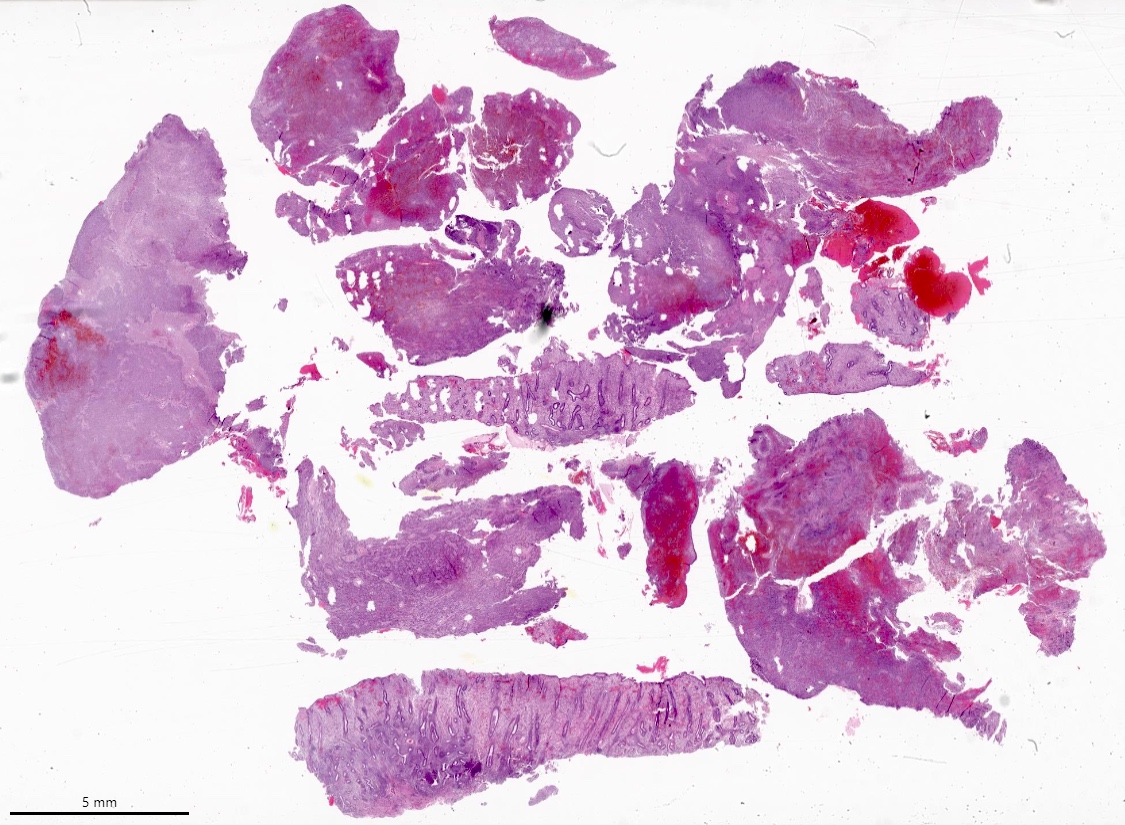

Gross images

Contributed by Elizabeth Kertowidjojo, M.D., Ph.D., M.P.H. and Ayse Ayhan, M.D., Ph.D.

Images hosted on other servers:

Microscopic (histologic) images

Contributed by Elizabeth Kertowidjojo, M.D., Ph.D., M.P.H. and Ayse Ayhan, M.D., Ph.D.